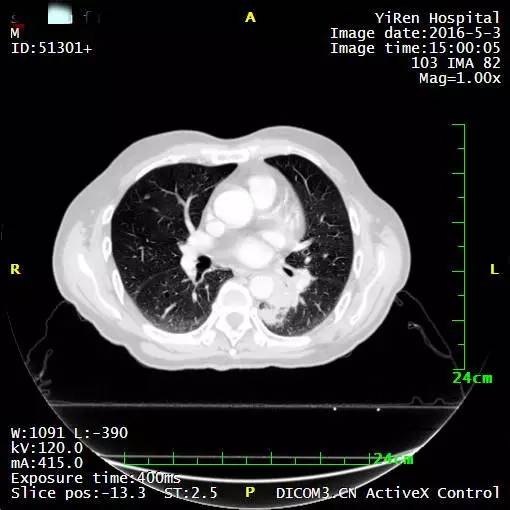

2016年3月,王先生因咳嗽加重就诊于当地医院,支气管镜病理检查提示:考虑小细胞癌的可能性大。

化疗一周期,病情无改善症状加重。

2016年4月,王先生接受了A45治疗,一个月后复查,病灶明显缩小,2016年7月复查,病灶进一步缩小,由于A45治疗具有明显的远观效应,能够激发自身的免疫系统,长期有效的消灭体内肿瘤,2016年12月,王先生肺部病灶几乎全部消失。

治疗前

治疗后